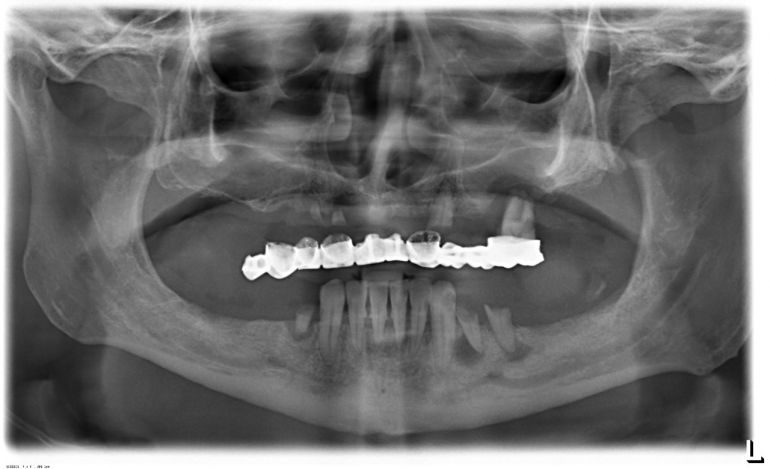

Πρακτικό και θεωρητικό σεμινάριο "Οδοντιατρική με άλλα μάτια: Η χρήση του μικροσκοπίου στην Οδοντιατρική"